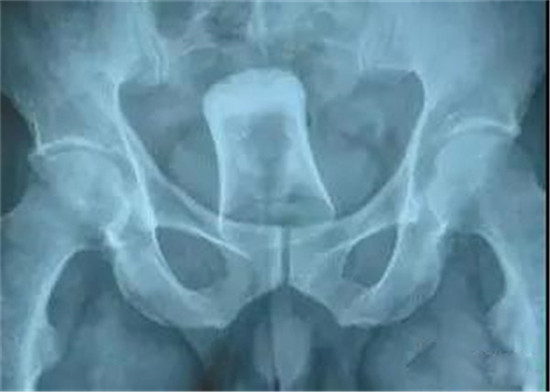

塞进直肠的灯泡。这个是女性病人。

塞进直肠的灯泡。

灯泡大头先塞进去,自己根本就取不出来。

也是一个白炽灯灯泡,是小头先塞进去。看出来男女了吗?